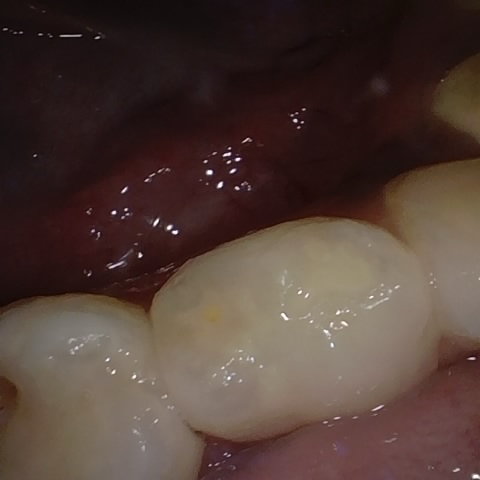

Annotated as "Good"